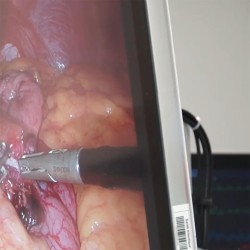

Get a sleeve in Tunisia (Endo Sleeve)

Decision to have a sleeve in Tunisia

The decision to undergo a Sleeve Tunisia operation is primarily motivated by the desire to lose weight, while also responding to health problems related to obesity and associated pathologies.